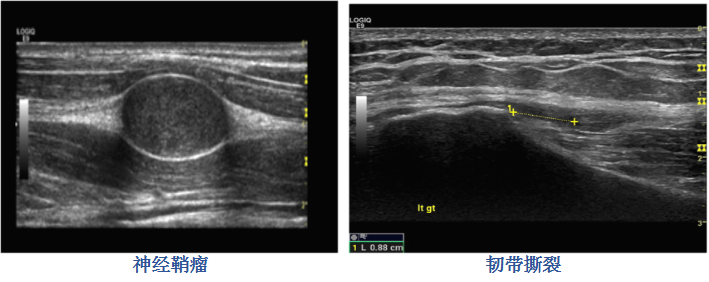

4、肌骨疾病:

對(duì)肌肉骨骼等一(yī)些(xiē)淺表組織具有(y≈<₹•ǒu)極佳的(de)成像效果,對(duì)細小(x∞λ≠‌iǎo)血供進行(xíng)觀察;彈性成像技(jì)術(shù)又(yòu)¥↔能(néng)對(duì)組織的(de)組織質地(dì)進行(xíng)觀察,φφ≥得(de)到(dào)組織變形的(de)佐證。

5、神經、肌肉骨骼、關節檢查:适用(yòng)于神經損傷、腫瘤病變,肌肉損傷,微(wēi)小(xiǎo)ε‌✘©骨折,關節病變等。